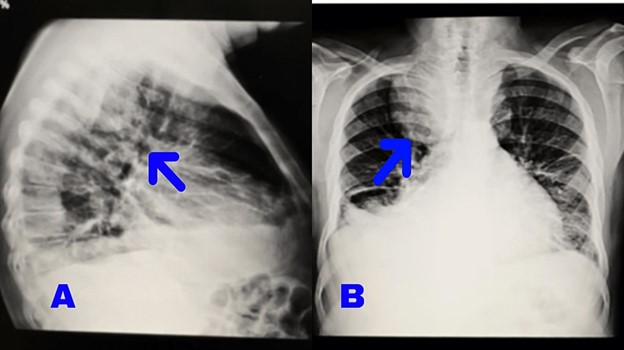

A 77-year-old male presented with severe productive cough symptoms that began three weeks ago. Initially, the patient experienced dry coughs, which progressively became more severe and productive, interfering with daily activities. Dyspnea with functional class 3 (FC 3) also developed over time, with the patient experiencing shortness of breath during daily activities and while lying down. The patient denied having a fever or any systemic symptoms. In the past medical history, the patient had undergone angiography because of exertional dyspnea FC 2 five years ago, and the result was normal angiography. His familial history was negative. He is a nonsmoker and has not been exposed to pollutants in his work or living environment. At the first examination, the patient’s heart rate was 88, respiratory rate was 22, blood pressure was 105/78 mmHg and blood oxygen saturation was 94%. During the physical examination, two-plus pitting edema was observed in the legs and feet, along with varicose veins. Decreased breath sounds were noticed in the lungs, particularly on the right lobe. Clubbing of the fingers was observed. The abdomen was soft, without tenderness or hepatosplenomegaly. Color Doppler sonography of the arteries and veins in the lower limbs revealed atherosclerotic changes in the arterial walls without significant plaque or narrowing. The presence of edema and fluid tracts in the distal part of both lower limbs suggested potential venous insufficiency. Electrocardiography showed evidence of atrial rhythm with a left bundle branch block (LBBB) view. Echocardiography reported biatrial enlargement, normal size of the left and right ventricles, mild mitral valve regurgitation, and a left ventricular ejection fraction (LVEF) of 60% with a left ventricular end-diastolic diameter (LVEDd) of 42 mm. A chest X-ray revealed a bilateral mass in the posterior mediastinum, with a larger size on the right side, as well as pleural effusion on the right side (Figure 1).

Figure 1. Posteroanterior and lateral chest X-ray shows bilateral posterior mediastinal mass and right costophrenic angle blunting.